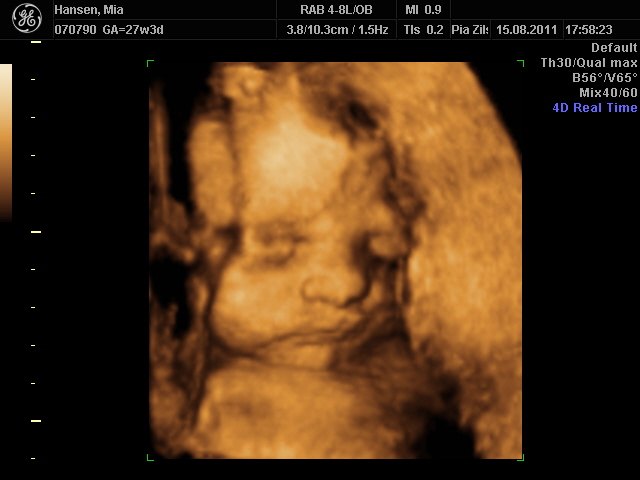

Fantastisk oplevelse. Lillepigen er bare så fin  en rigtig putte-pige

her kommer lidt billeder

Mia 27+3